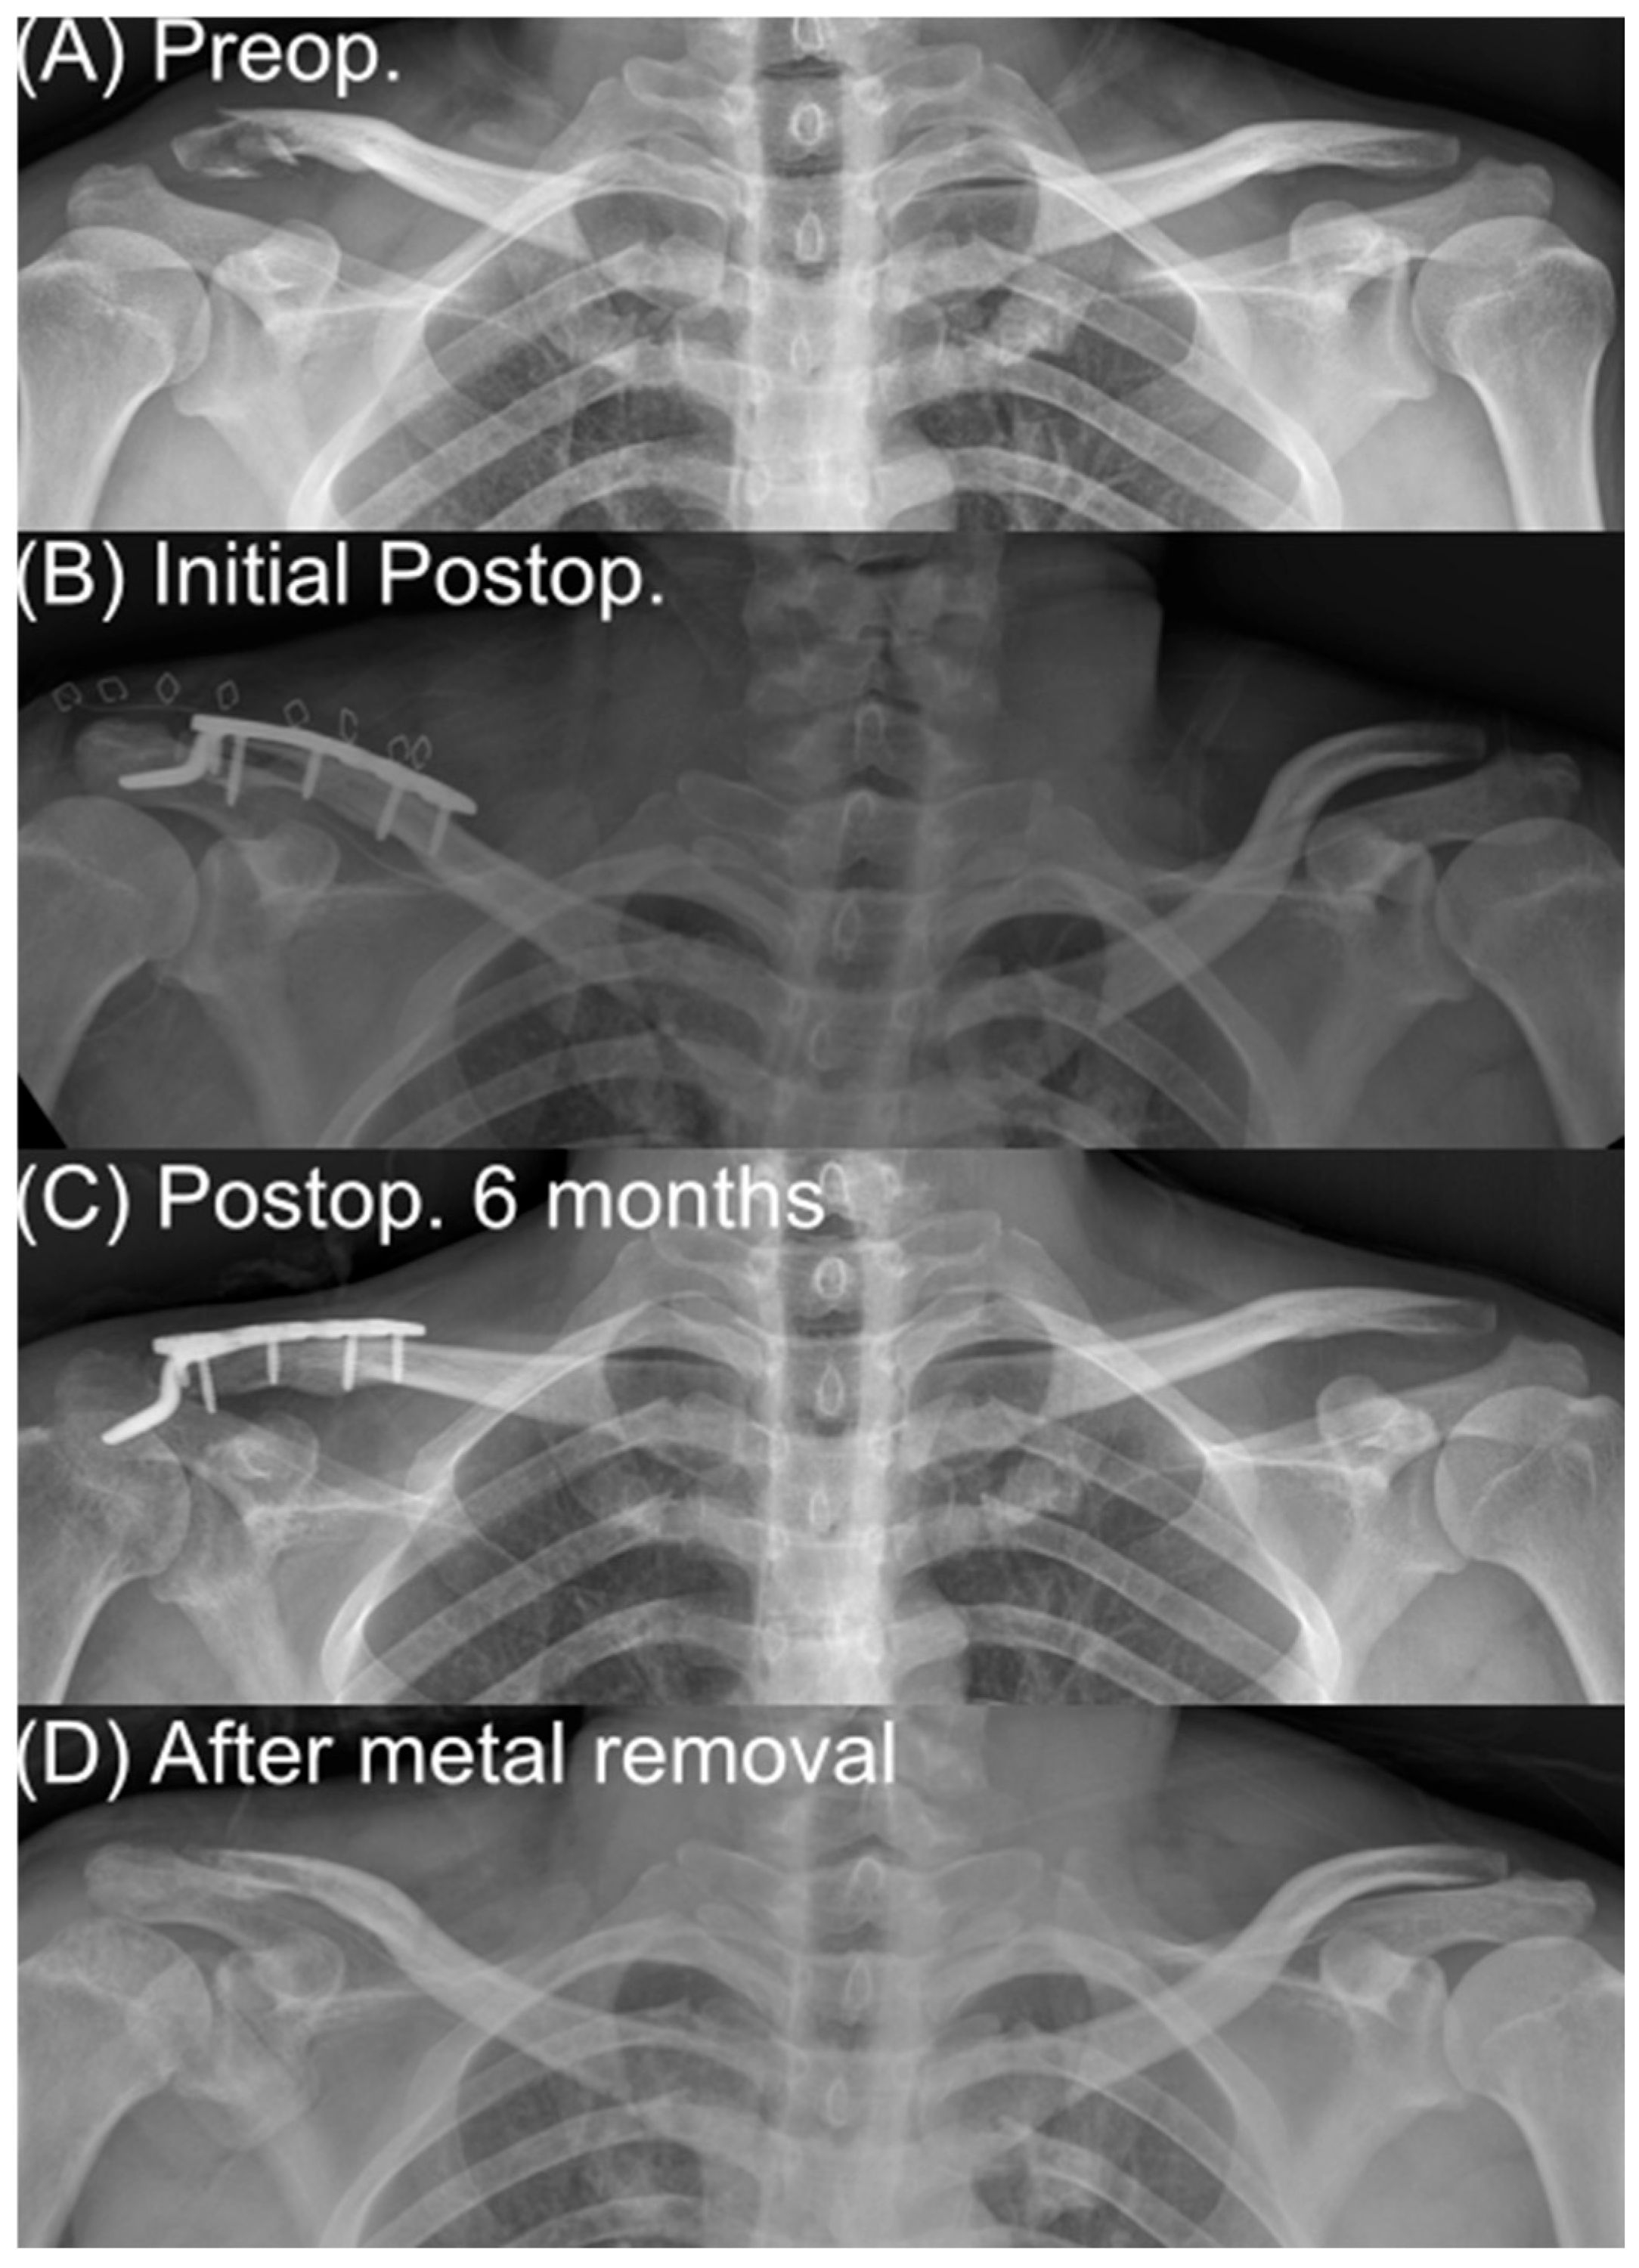

A 31-year-old man who sustained a right distal clavicle fracture in a traffic accident was treated with distal clavicle locking plate fixation with supplementary fragment-based cerclage. (A) is a preoperative anteroposterior radiograph showing an unstable distal clavicle fracture. (B) is a three-dimensional reconstructed CT image demonstrating displacement and comminution of the distal fragment. (C) is an immediate postoperative radiograph demonstrating anatomic reduction and fixation with a precontoured distal clavicle locking plate and stainless-steel cerclage applied around the distal fragments and proximal clavicle (without encircling the coracoid). (D) is a radiograph obtained 6 months postoperatively showing maintained reduction and solid bony union.